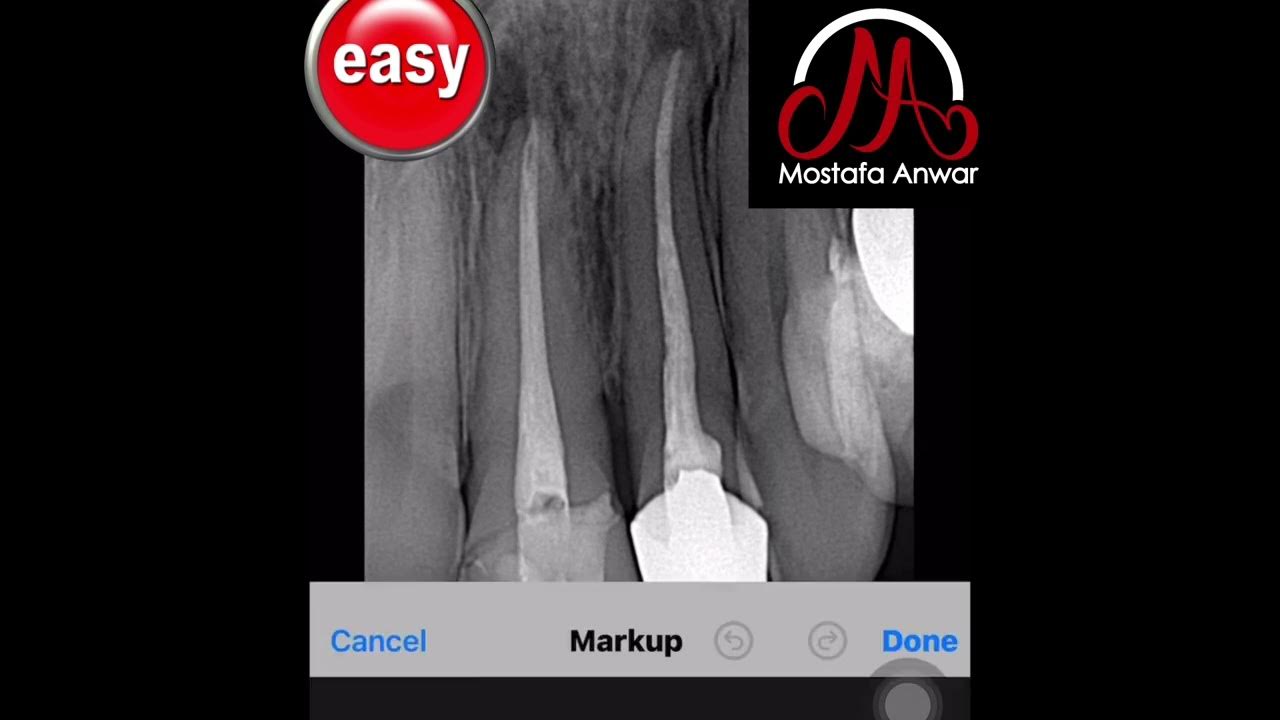

How to Remove Gutta Percha during Retreatment of Upper Central Incisor

How to Remove Gutta Percha during Retreatment of Upper Central Incisor How To Remove Gutta Percha From Root Canal With good case selection, niti. This video demonstrates the retreatment and removal of gutta percha in endodontic dentistry. What are the various methods to remove gutta percha from a root canal? This article has reviewed the common techniques for removal of gp during endodontic retreatment with a focus on atraumatic removal of gp using heat, mani gpr files, h files,. How To Remove Gutta Percha From Root Canal.